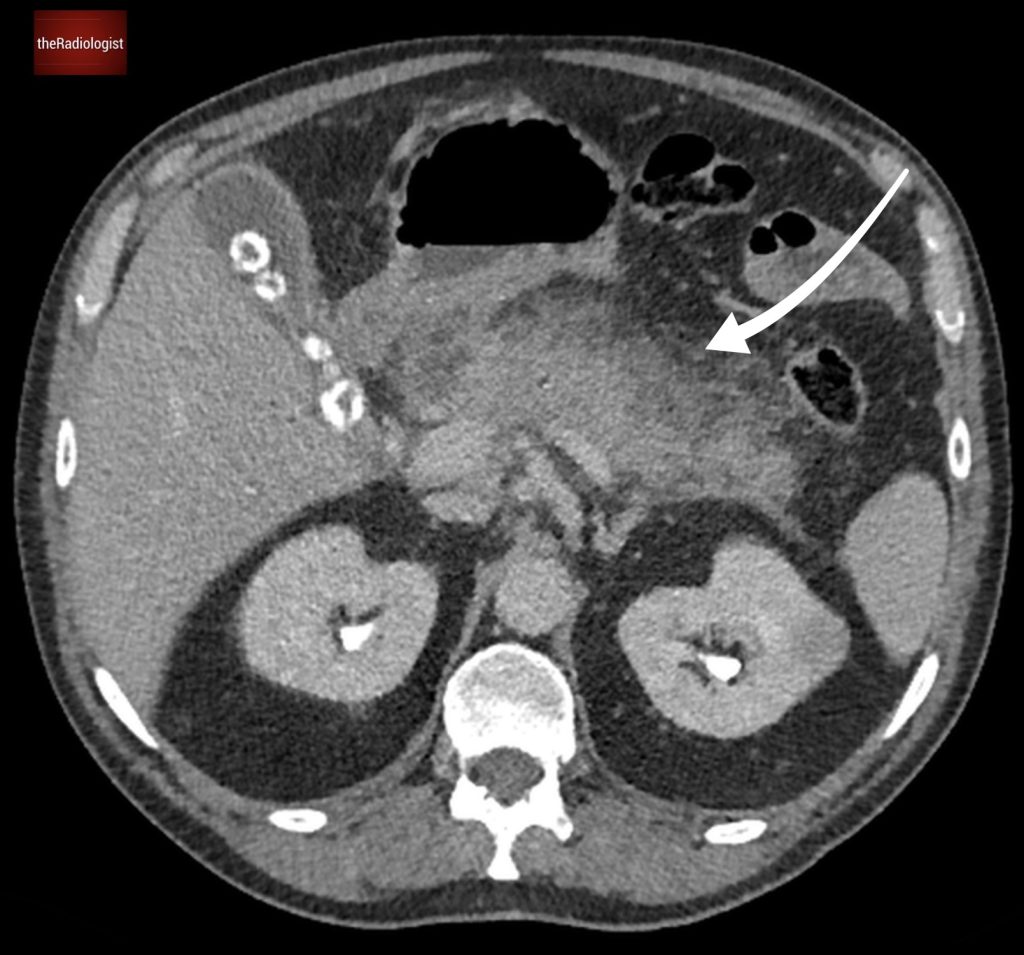

If we look at the psoas muscles on this scan below we can see there is some asymmetry . The right psoas is larger than the left and we’ve lost some of the fat planes within the muscle.

Compare the psoas muscles side by side. The right sided psoas muscle appears expanded with a loss of its normal fat planes.

Also as we scroll down we can see there is fat stranding surrounding the psoas muscle extending into the pelvis.

There is fat stranding surrounding the psoas extending into the pelvis.